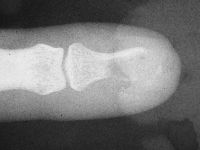

| Xrays show loss of much of the distal half of the distal phalanx, with cortical disruption. |